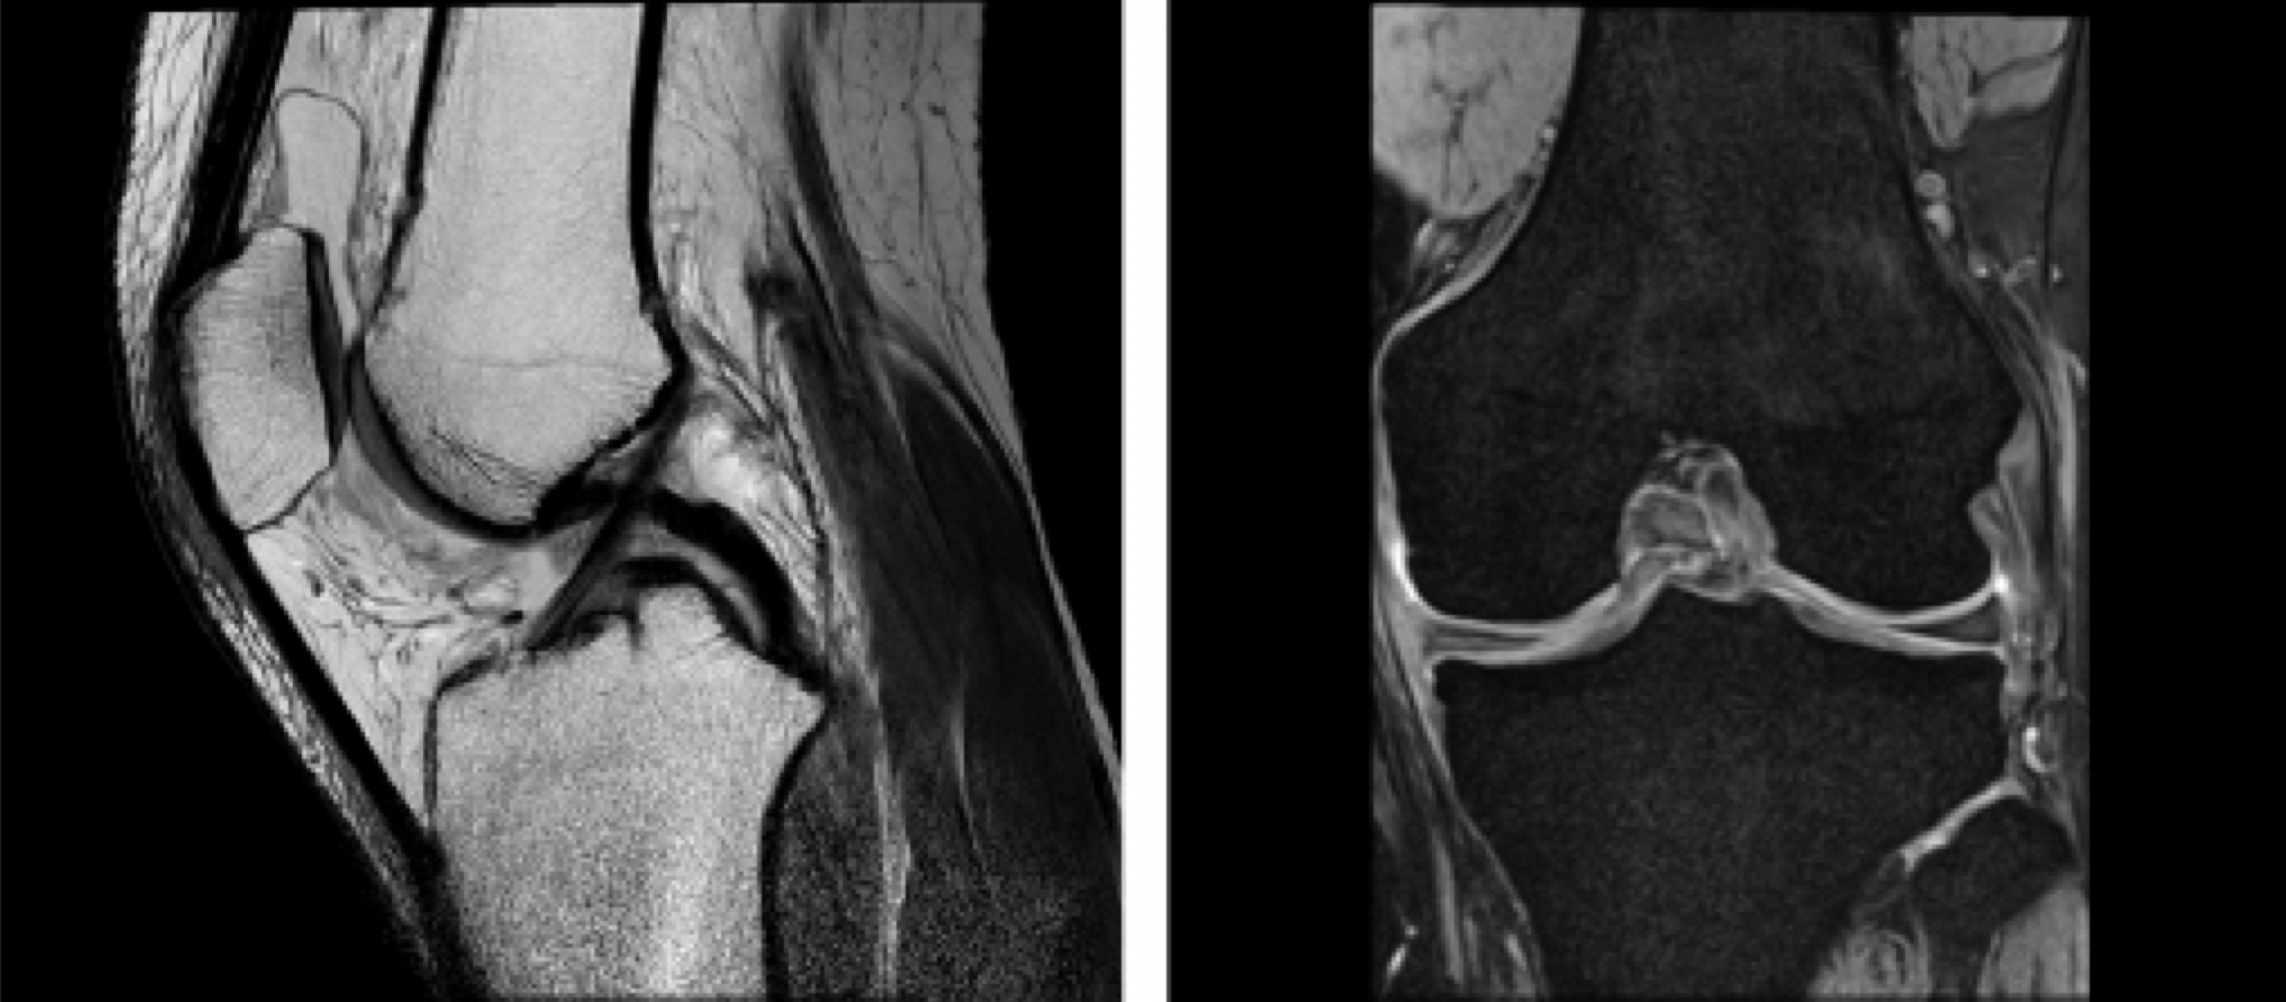

検査時間が短く、高性能、高画質の1.5テスラMRI装置を導入しています。

膝関節